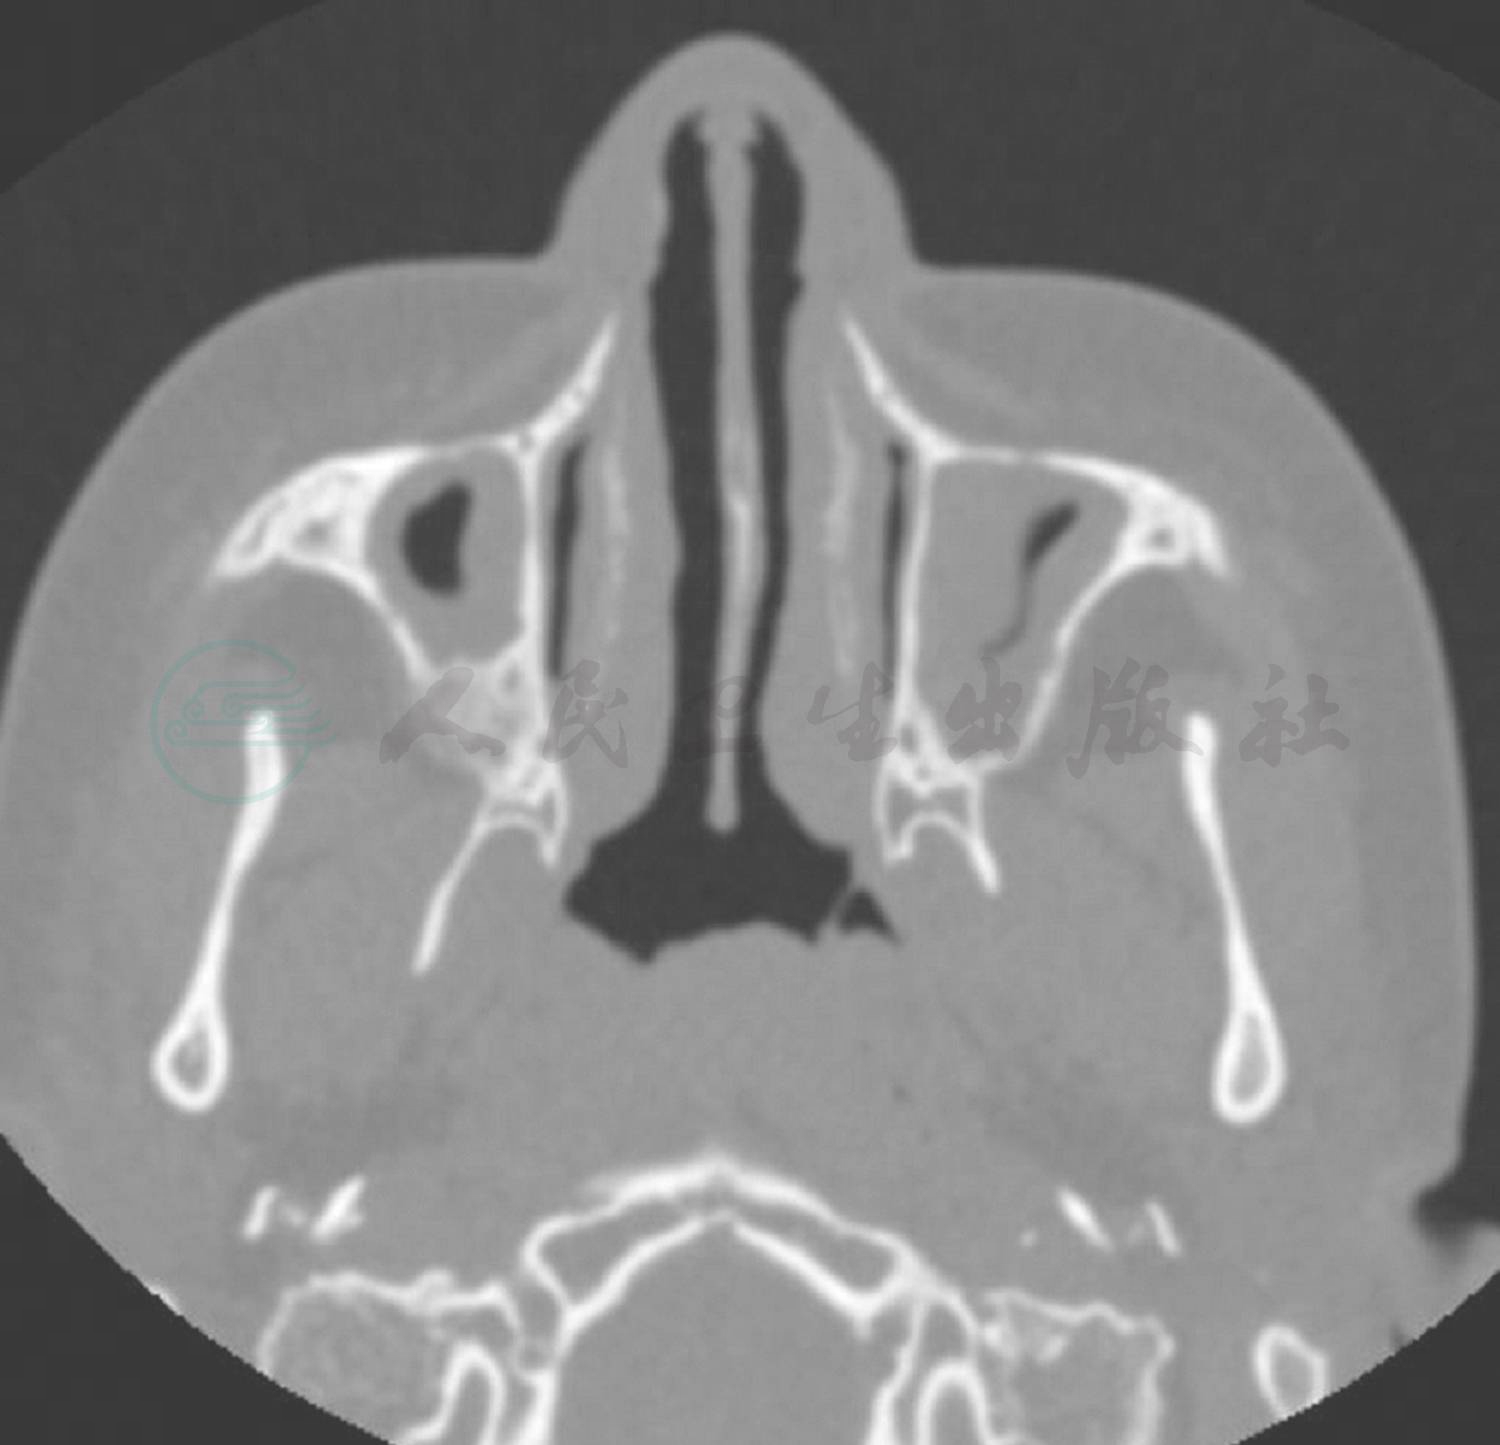

入院后完善相关检查,考虑支气管扩张患儿肺部铜绿假单胞菌等革兰氏阴性杆菌定植后感染较多见,经验性予头孢他啶抗感染,同时予大环内酯类抗生素口服抗感染治疗。入院后查血常规+CRP正常,血沉45mm/h(升高),LDH 847U/L(升高),肝肾功能、血清铁蛋白及降钙素原正常,呼吸道病毒抗体、肺炎支原体、衣原体、嗜肺军团菌阴性,痰培养呼吸道正常菌丛生长,未检出明确病原菌。入院后完善胸部HRCT检查,所见(图1)左肺上叶舌段、下叶及右肺下叶可见散在粟粒状渗出影及“树芽征”,右肺中叶见片状渗出影,右肺中、下叶部分支气管扩张、管壁增厚,部分管腔内见黏液栓。根据胸部CT表现,临床思考:①两肺散在粟粒状渗出影和小结节影以及“树芽征”,提示累及细支气管的炎症渗出或分泌物堵塞,考虑到患儿同时存在慢性鼻窦炎,需注意弥漫性泛细支气管炎的可能,予以完善副鼻窦CT及冷凝集试验;②存在结核感染可能,应详细询问排除结核接触史,并完善结核感染T细胞测定、肺泡灌洗液抗酸染色及结核分枝杆菌DNA定量等检查;③真菌感染表现不典型,可行真菌1,3-β-D葡聚糖试验辅助诊断;④注意肺囊性纤维化、原发性纤毛运动障碍及先天性免疫缺陷等少见病的可能,完善细胞体液免疫功能、血淀粉酶检测,亦需进行副鼻窦CT检查,同时在支气管镜检查中进行支气管黏膜活检电镜检查;⑤应继续完善病原学的检测,予以支气管镜检查及支气管肺泡灌洗。患儿入院第4天行支气管镜检查,术中发现患儿气道结构正常,右主支气管、右肺中叶及左主远端支气管内较多白色黏稠分泌物附着,阻塞部分支气管开口,予以吸引干净后在上述支气管开口处做支气管肺泡灌洗,回收灌洗液送培养和相关病原学检测。并分别在右肺中叶支气管、左主远端支气管开口取活检,送电镜纤毛检查。入院第5天,患儿咳嗽减轻,咳痰减少,肺部啰音减少。但前述各项检查中,除外副鼻窦CT平扫(图2)示全鼻窦炎,窦内分泌物密度较高,其余血清学检查、肺泡灌洗液检查、纤毛电镜检查及基因检查(罕见遗传病基因测序)均未见异常。与患儿及家属充分讨论后,于入院第13天行肺活检术,手术顺利,术后恢复可。肺组织病理检查(右肺)(图3)提示淋巴组织增生相关疾病(滤泡性细支气管炎,部分区域呈淋巴细胞间质性肺炎改变)。同时完善自身免疫疾病抗体全套检查,其中ANA 1:320(阳性),余抗体阴性。入院第19天患儿病情稳定出院,出院后长期口服小剂量红霉素抗炎,口服细菌溶解产物调节免疫功能,雾化吸入乙酰半胱氨酸化痰,并嘱每日体位引流及震动正压通气装置呼吸锻炼2~3次,风湿科及呼吸科定期随访。目前随访至出院后5个月,期间短时发热2次,未予特殊处理自行恢复,咳嗽咳痰好转,近2个月体位引流排痰量较前减少,活动耐力较前增加,随访6分钟步行试验达年龄预计值81.8%(病初56%),生长发育良好。

图2 入院后鼻窦CT提示:全鼻窦炎,窦内分泌物密度较高